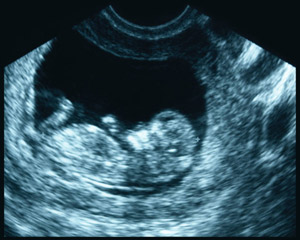

Why an Ultrasound?

At Pregnancy Services, complimentary ultrasounds are available to all women to confirm the pregnancy. All ultrasound examinations performed on patients at a pregnancy help medical clinic, like this one, are limited obstetrical ultrasounds. The purpose of such an ultrasound is to confirm the viability of the pregnancy and ensure that the client is not in danger of a miscarriage. (If there is risk of miscarriage, immediate medical attention is warranted.)

Once the pregnancy is confirmed, the client will truly be able to consider her options and make a decision. No one option is right for everyone — our goal is to help the client explore her individual situation and provide education to aid in the decision-making process.